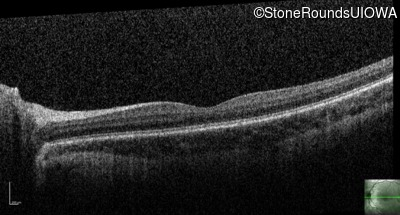

Blue Cone Monochromacy (IA2e)

Age at visit: 7 years

This 7 year old boy had nystagmus first noticed at 4 months of age.

Blue Cone Monochromacy L/M OPSIN Cluster Promoter Deletion LCR   XL